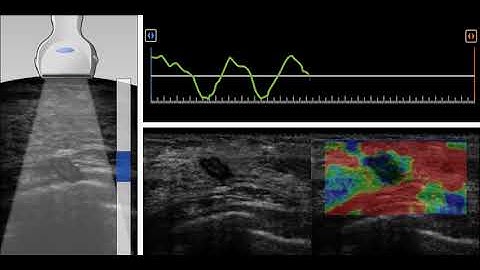

How to Perform VShear & Point VShear | Shear-Wave Elastography Tutorial